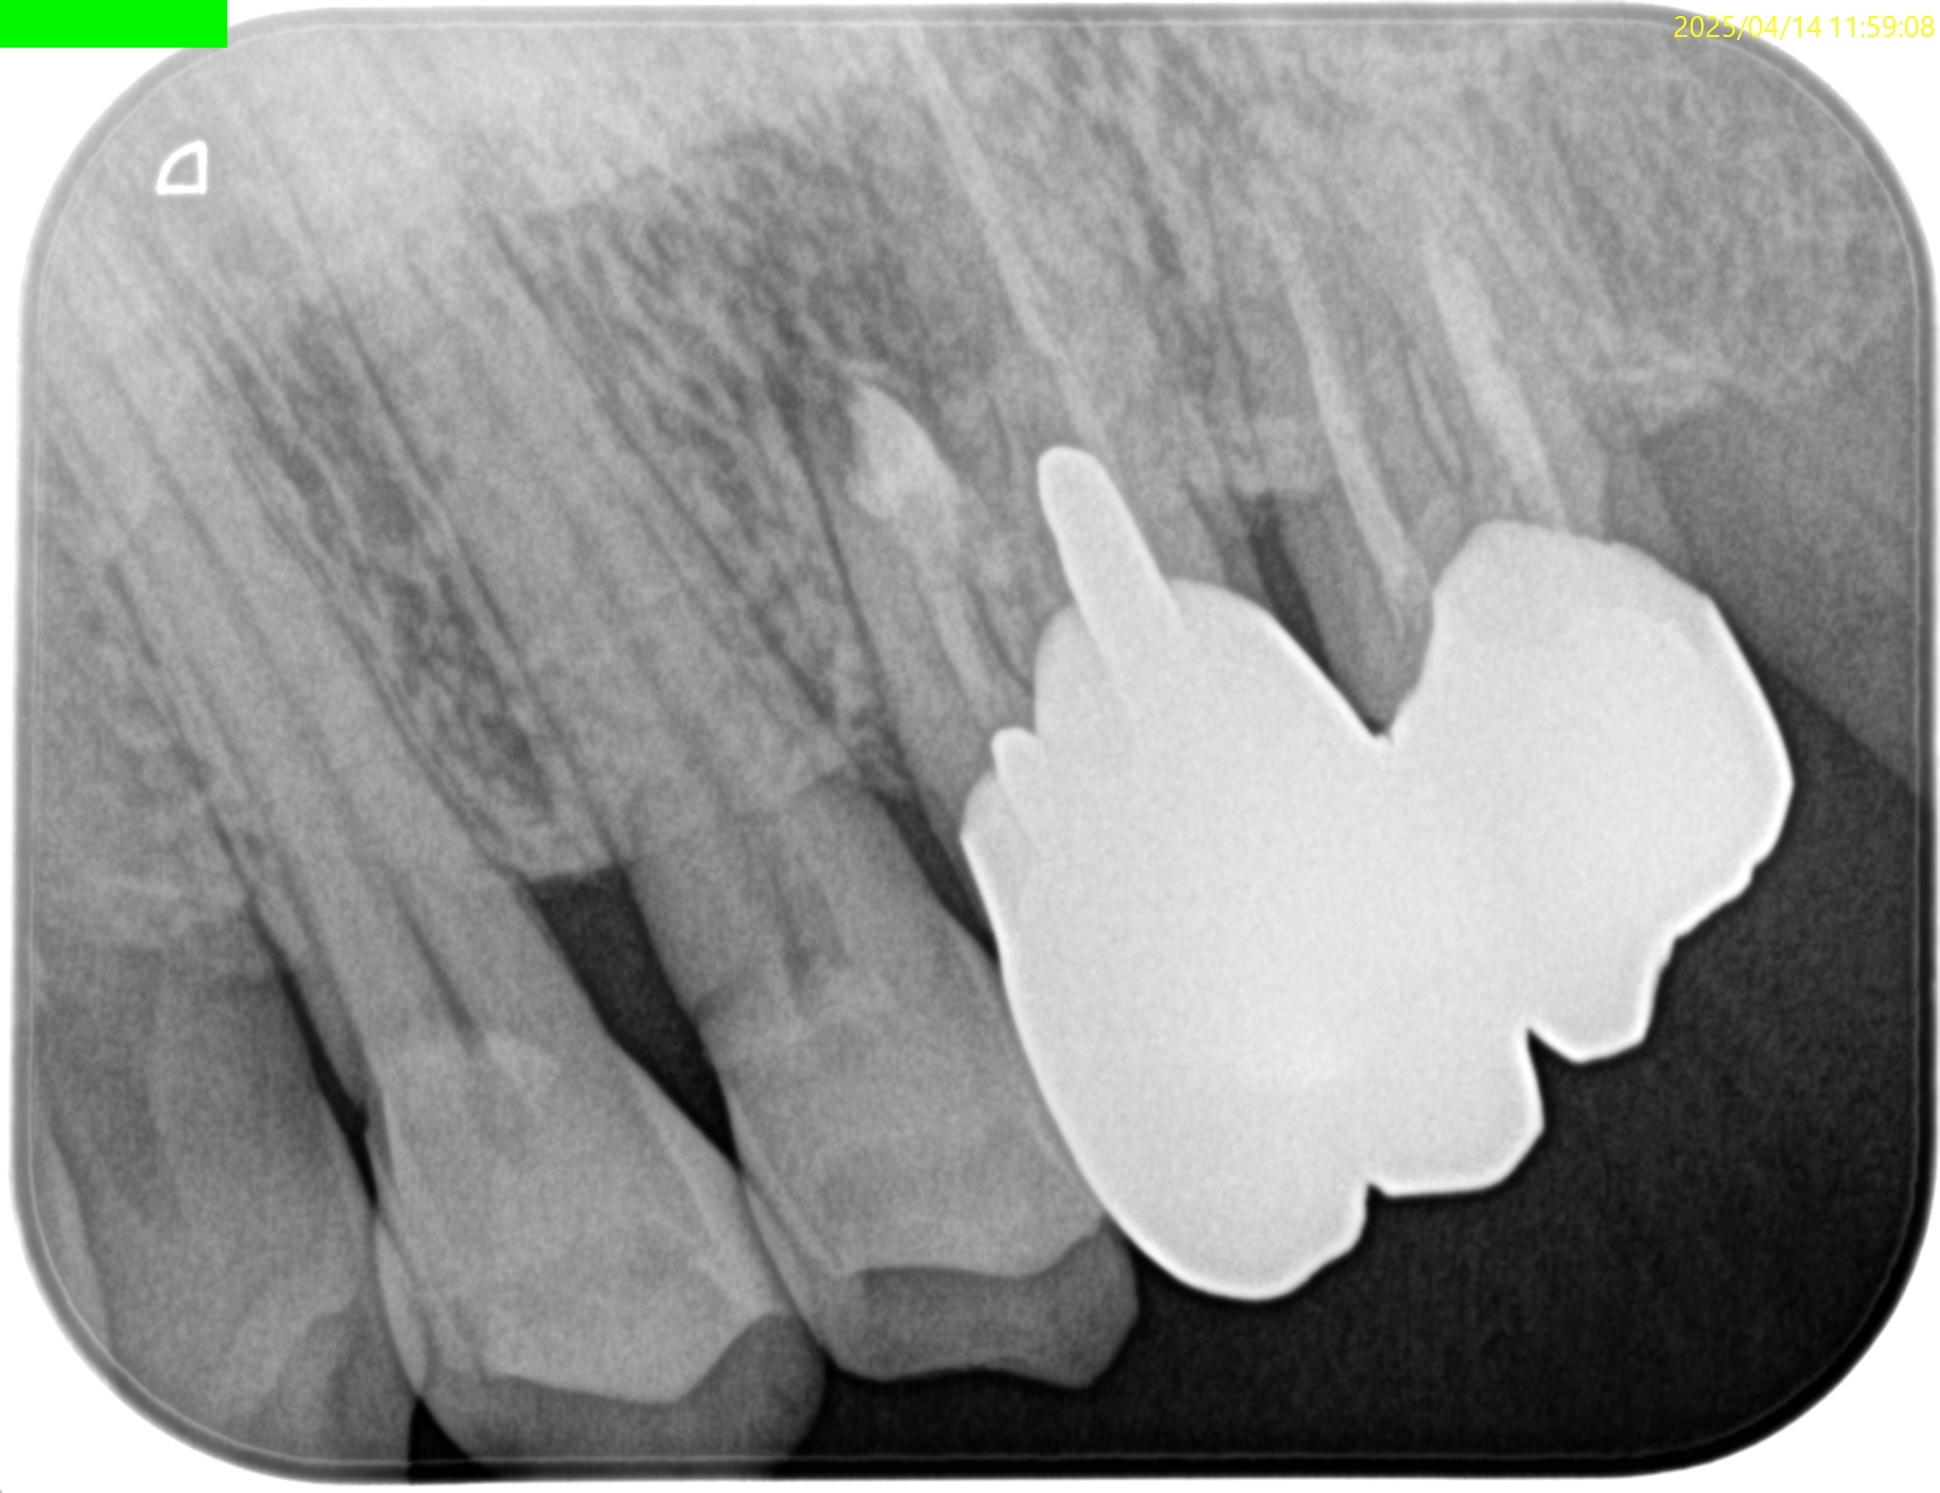

MB

B

逆根管充填材は逆根管形成で穿孔させたが即日修復=充填しているので問題ないだろう。

最後に縫合して終了した。